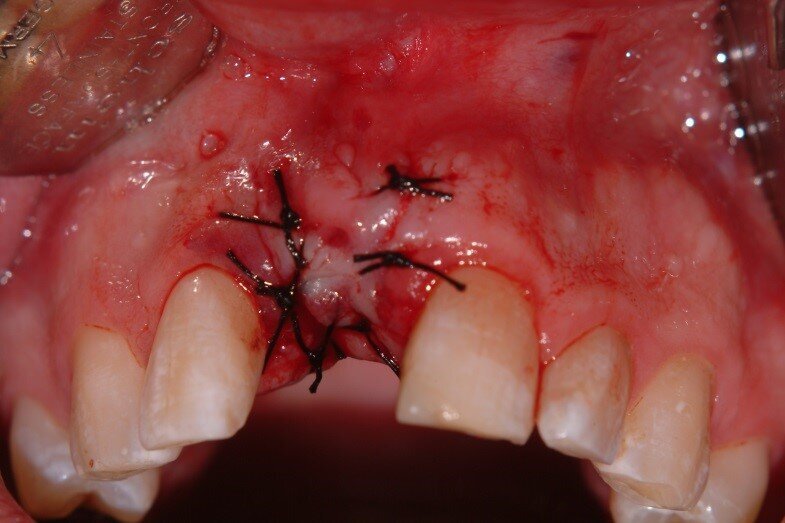

5. Bilateral pedicles using adjacent papilla to cover the connective tissue surfaces of the tuberosity graft (Fig. 5)

5. The flap was sutured with 4-0 silk to achieve primary closure over the site. (Fig. 11)